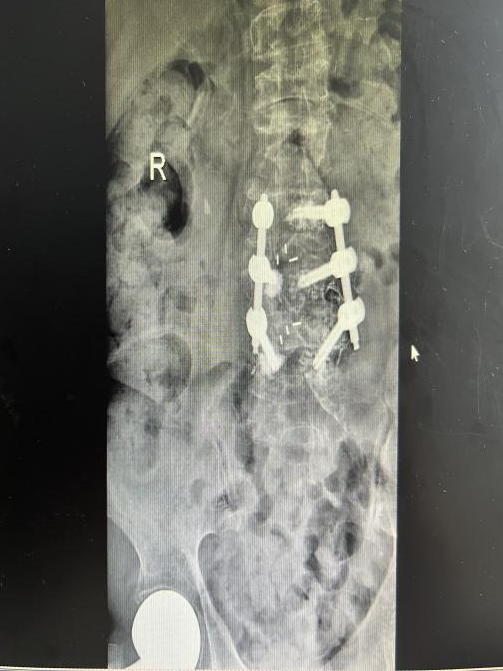

2025年11月1日,由遵义市医学会手外科分会主办、遵义市第二城市医疗集团(贵州航天医院)承办的遵义市医学会手外科分会学术交流会暨贵州省继续医学教育项目《急诊手外伤治疗临床研究新进展专题研讨班》在贵州航天医院成功举办,汇聚了遵义市手外科领域专家及基层医疗骨干,通过专题研讨与临床经验分享,共探急诊手外伤诊疗新进展。 会议特邀遵义市医学会手外科分会主任委员金文虎教授,遵义市医学会手外科分会副主任委员张子阳教授,遵义市医学会手外科分会常务委员杨绍浦教授,贵州航天医院陈明勇教授、赵兴东教授等遵义市手外伤专家进行交流分享;贵州航天医院党委委员、副院长彭亮参加会议并致辞,贵州航天医院骨科医务人员,遵义市第二城市医疗集团成员单位及红花岗区、绥阳县、桐梓县等区县医疗机构手外伤骨干参与。 贵州航天医院党委委员、副院长彭亮致辞 学术交流 本次学术交流以“急诊手外伤治疗临床研究新进展”为主题,通过理论授课与临床案例结合,共同探讨急诊手外伤临床诊疗全链条诊疗策略、关键技术、临床研究新进展,促进规范化诊疗技术向基层下沉,助力提升区域手外伤应急处置与修复能力。 贵州航天医院赵兴东教授分享《急诊手外伤的诊断与治疗原则》 贵州航天医院陈明勇教授分享《开放性骨折的治疗原则》 贵州航天医院张军教授分享《甲沟炎Winograd手术的临床应用》 贵州航天医院赵兴东教授分享《手部常见的皮肤缺损及治疗原则》 贵州航天医院张艳金教授分享《开放性骨折的清创术》 贵州航天医院冷家雄教授分享《下肢创面修复的常用皮瓣之股前外侧皮瓣》 贵州航天医院邬夏荣教授分享《踝关节慢性不稳的诊治》 贵州航天医院卢懿明教授分享《掌骨骨折》 贵州航天医院张艳金教授分享《手部肌腱的解剖与修复方法》 本次研讨班为遵义市手外科领域医务人员提供了深度交流契机,强化了医疗机构间的协作网络,进一步推动学科创新与临床实践融合,为健康遵义建设注入新动能。 贵州航天医院骨科专家简介 陈明勇 骨一科主任,副主任医师 临床擅长:从事创伤骨科工作约20年,对骨缺损、骨不连、骨肿瘤、肢体畸形等的肢体矫形重建及功能重建,慢性化脓性骨髓炎的根治治疗、糖尿病足的保肢治疗、快速康复理念(ERAS)下的老年骨折的诊治,四肢复杂骨折的诊治,四肢骨折等微创手术治疗具有丰富的临床经验。 2004年毕业于遵义医学院临床专业,曾在中国人民解放军总医院、广西医科大学第一附属医院、上海第六人民医院骨科进修。中国中西医结合学会骨伤科专业委员会横向骨搬移治疗糖尿病足及微血管网再生学组首届委员,遵义市医学会创伤分会常务委员。 瞿 晖 骨科党支部书记,骨二科主任,副主任医师 临床擅长:对骨科的常见病、关节外科、脊柱外科及运动医学疾病的诊治具有丰富的临床经验,熟练掌握骨科手术操作技术。 毕业于遵义医学院临床医学系,2005年前往广州中山大学第一附院骨显微医学部进修学习,2011年前往成都华西医院进修学习,并多次在省内外学习骨科相关知识,是中华医学会骨科分会会员。 赵小锋 中共党员,骨二科副主任,副主任医师 临床擅长:从事骨科临床工作11年,对骨科常见病、多发病诊疗有较为丰富的临床经验,擅长脊柱相关疾病诊断及治疗,尤其是颈、腰、腿疼痛疾病诊断及治疗,擅长胸腰椎骨折微创经皮穿刺内固定术、经皮穿刺椎体成形术、经皮穿刺脊柱内镜下腰椎间盘摘除术、单纯开创腰椎间盘摘除术、腰椎滑脱复位椎间植骨椎融合内固定术、腰椎管狭窄减压融合内固定术及人工髋、膝关节置换术等。 2012年毕业于遵义医学院外科学专业硕士研究生,2019年参加“遵义市115医学人才精英计划”于上海交通大学第一附属医院培训学习,2023年于北京大学第三人民医院脊柱外科进修学习,曾获得遵义市优秀医师荣誉称号。 遵义市手外科第一届委员,遵义市医学会创伤分会第一届委员,遵义市医学会创伤分会第二届委员,贵州省康复医学会第三届脊柱脊髓专业会委员,遵义市医学会烧伤与整形外科学分会委员,发表论文5篇,其中国家级核心期刊1篇,SCI论文1篇,主持市级课题1项并结题,参与市级课题2项。 赵兴东 骨科主任医师 临床擅长:擅长骨科的常见病及各种创伤、四肢骨折创伤修复、骨感染、手足疾病的诊治和手足体表畸形的矫形整复,熟练掌握骨科四肢骨病及创伤的手术操作技术,尤其在四肢关节复杂性损伤、手足外伤、组织缺损创面、难治创面的皮瓣修复方面及平足、高弓足矫形方面及四肢慢性疼痛诊治、康复方面具有丰富的临床经验。 硕士研究生,毕业于遵义医学院临床外科系,2015年前往山东省立医院手足外科进修学习;遵义市医学分会创伤分会第一、二届委员,遵义市手外科医学会第二委届员会常务委员;在省级及省级以上期刊发表文章9篇,参编著作2部,参与主持并完成市级课题1项,参与市级课题2项、省级课题1项。 张艳金 中共党员,骨科副主任医师 临床擅长:从事骨外科工作16年,对复合伤、多发伤的救治、四肢骨干骨折、关节周围骨折、骨肿瘤、骨髓炎等诊治具有丰富的临床经验。 中共党员,硕士研究生,2006年本科毕业于山西医科大学第二临床医学院,2011年研究生毕业于北京军区总医院;在“老年COPD患者合并髋部骨折的诊治”国际合作课题组研究两年,在老年髋部骨折的诊治方面具有丰富的经验,并发表论文6篇;主持遵义市级课题1项,承担遵义医科大学的临床教学工作,获得遵义医科大学优秀带教老师荣誉。编撰有《骨科疾病诊疗精粹》一书,开展2项新技术,编撰地方规范《务川自治县创伤骨科常见疾病诊疗规范》一书。 张俊凯 骨科副主任医师 临床擅长:从事骨科临床工作28年,对创伤骨折、骨感染、骨缺损、骨不连等外科诊治,四肢骨折的微创手术治疗,四肢复杂骨折(如关节内粉碎性骨折、多发骨折等)的损伤控制及手术治疗等具有丰富的临床经验。 1995年毕业于遵义医学院临床专业,2009年前往复旦大学附属医院骨科进修1年。 卢懿明 中共党员,骨科副主任医师 临床擅长:从事骨科工作18年,对创伤骨折、四肢骨折的微创手术治疗、四肢复杂骨折(如关节内粉碎性骨折、多发骨折等)的损伤控制及手术治疗,尤其是髋部骨折的PFNA等微创技术,踝关节骨折、膝关节周围骨折的Mipo微创技术等具有丰富的临床经验,开展了4项新技术,发明6项新型专利技术。 2005年毕业于遵义医学院临床专业,2017年,前往南方医科大学第三附属医院骨科进修半年,回院后运用Mipo技术对骨干骨折及干骺端骨折的治疗技术,同时积极开展骨盆骨折、髋臼骨折腹直肌外侧切口的应用;发表了多篇专业论文,经常参与省内外学术交流会授课,获得医院荣誉称号多个。 邬夏荣 骨科副主任医师 临床擅长:从事骨科工作16年,对四肢复杂骨折、骨肿瘤的诊治,尤其是足踝创伤、慢性踝关节损伤、平足症等诊疗具有丰富的临床经验。 2006年毕业于遵义医科大学临床医学专业,曾在陆军军医大学西南医院进修学习,发表多篇骨科学术论文。 余德怀 中共党员,骨科副主任医师 临床擅长:从事骨科工作10余年,对运动医学、骨关节、脊柱外科常见病、多发病的诊治具有丰富的临床经验。 硕士研究生,2011年毕业于遵义医学院临床医学专业,曾前往遵义医科大学附属医院运动医学专业进修学习;是贵州省医学会运动医学分会青年委员,西部关节镜联盟委员;发表多篇骨科学术论文。 冯 乾 骨科副主任医师 临床擅长:从事骨科工作近20年,熟练掌握骨科多发病及常见病的诊治,尤其对脊柱退变性疾病的诊断及治疗具有丰富的临床经验,主要研究脊柱微创相关治疗方式,能熟练开展椎间孔镜及UBE。 曾前往北京大学第三医院进修学习疼痛及椎间孔镜、首都医科大学友谊医院专业进修脊柱内镜;是贵州省康复医学会第三届脊柱脊髓专业委员会委员;发明专利3项、发表脊柱外科专业论文多篇。 贵州航天医院骨科简介 基本情况 贵州航天医院(原3417医院)骨科组建于1968年,前身是以创伤和断肢(断指)再植闻名于世的上海市第六人民医院骨科,中国断肢(断指)再植的奠基者、中科院院士陈仲伟等专家莅临科室指导医疗和教学,并在70年代开展了贵州省首例断肢(断指)再植手术。组建50余年来,诊治患者已逾百万,挽救了无数的伤病员,成为了保障遵义地区人民群众健康的重要支撑。 经过几代人的不懈努力,今天的骨科,已由创伤骨科发展至骨病、骨肿瘤、骨结核等领域,现有脊柱外科、关节外科、四肢创伤、手足外科四个亚专科,成为了集医疗、教学、科研于一体的综合学科,是贵州省临床重点专科、遵义市临床重点专科、遵义市骨科临床医学中心、遵义市基层骨科专科联盟理事长单位。 科室目前开放床位110张,共有医护人员50余人,副高级以上专家18人,硕士研究生15人。拥有一流骨科医疗设备多台,每年不定期选派优秀技术骨干到全国各大知名医学院校进修、学习、参观、交流,并邀请国内、国外知名专家教授来院进行交流、指导,通过不断引进国内外先进的诊疗技术,科室医疗技术水平稳步提升,为广大人民群众提供了优质的医疗服务。 专科特色 骨一科 (一)骨缺损、骨不连的肢体与功能重建 胫骨横向骨搬移技术治疗糖尿病足: (二)慢性骨髓炎的根治治疗 (三)肢体缺血性疾病如糖尿病足、脉管炎的保肢治疗 (四)皮瓣修复 (五)复杂创伤的治疗 (六)老年髋部骨折及小儿骨折快速手术 老年髋部骨折: 骨二科 (一)胸腰椎骨折微创经皮椎弓根螺钉固定术 (二)老年性骨质疏松性患者腰椎滑脱脊柱内固定术(骨水泥螺钉) (三)V形双通道脊柱内镜技术(VBE)腰椎融合术治疗腰椎退行性疾病 (四)老年性骨质疏松性骨折(PVP/PKP)术 (五)人工髋关节置换术 (六)双侧股骨头坏死人工全髋关节置换 (七)右侧全髋置换术后假体周围骨折翻修 (八)人工膝关节置换术 (九)人工膝关节假体松动翻修 (十)关节镜技术 传统手术切口 关节镜技术切口 诊疗范围 骨一科 1.四肢创伤、矫形。 2.手、足踝外科。 骨二科 End